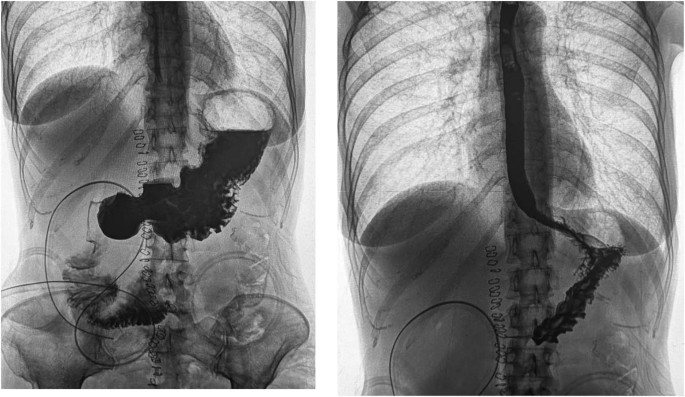

In a compelling case report, a 53-year-old female with severe malnutrition and a high-output duodenal stoma experienced a remarkable transformation with teduglutide treatment. Despite having only 5 cm of remaining small bowel, the patient's stoma output reduced from 6-12 L/day to 2.5-3 L/day within two months of teduglutide initiation. This not only stabilized electrolyte balance but also led to a notable 3-4 kg increase in body weight.